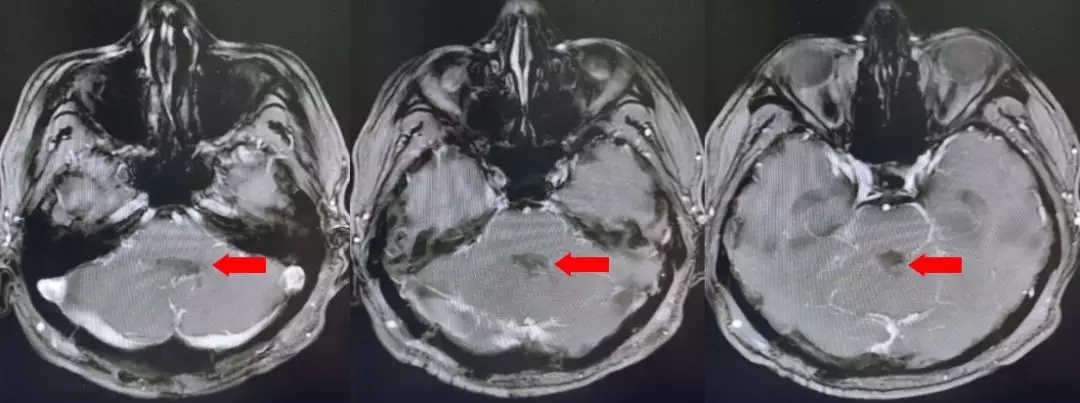

颅脑核磁T1W1成像

颅脑核磁增强扫描

颅脑核磁平扫加增强扫描:

第四脑室内见一巨大形态不规则的异常信号影,肿瘤信号不均匀,T1W1呈略低信号影,T2W1呈稍高及高信号影,增强扫描可见肿瘤不均匀明显强化。肿瘤充满整个四脑室,大小约44*37*55mm,上方接近四脑室顶部,下方至颈2脊髓平面上方,已经部分侵袭桥脑、延髓,局部边界不清,无明显间隙,脑干局部明显受压变形。肿瘤上方脑室系统扩张,出现梗阻性脑积水征象。

影像诊断:1.第四脑室内占位性病变,室管膜瘤可能性大;2.梗阻性脑积水。